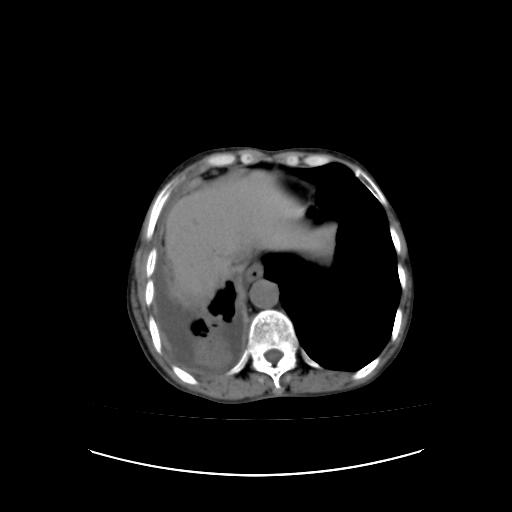

右侧胸膜转移瘤,原发灶可能就在在右肺,另外建议检查右侧乳腺.

胸膜转移瘤  包裹性胸腔积液  肺内转移